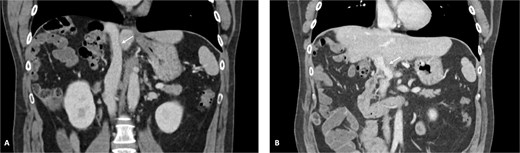

The patient was discussed at a multidisciplinary meeting for suspected intrahepatic cholangiocarcinoma. Due to the tumour size and macrovascular invasion, the patient was proposed for neoadjuvant treatment. After a biopsy confirmed the diagnosis, the patient underwent three cycles of gemcitabine and cisplatin, resulting in a reduction of the cholangiocarcinoma from the maximum longitudinal diameter of 12.6 to 7.5 cm (Fig. 2). An extended right hepatectomy with resection and reconstruction of the PV and IVC using an APFP was then proposed.

CT scan of the intrahepatic cholangiocarcinoma after chemotherapy. (A) Axial CT scan showing cholangiocarcinoma diameter reduction after chemotherapy and (B) and (C) coronal CT scan view of the vascular relation between the cholangiocarcinoma, IVC, and PV.